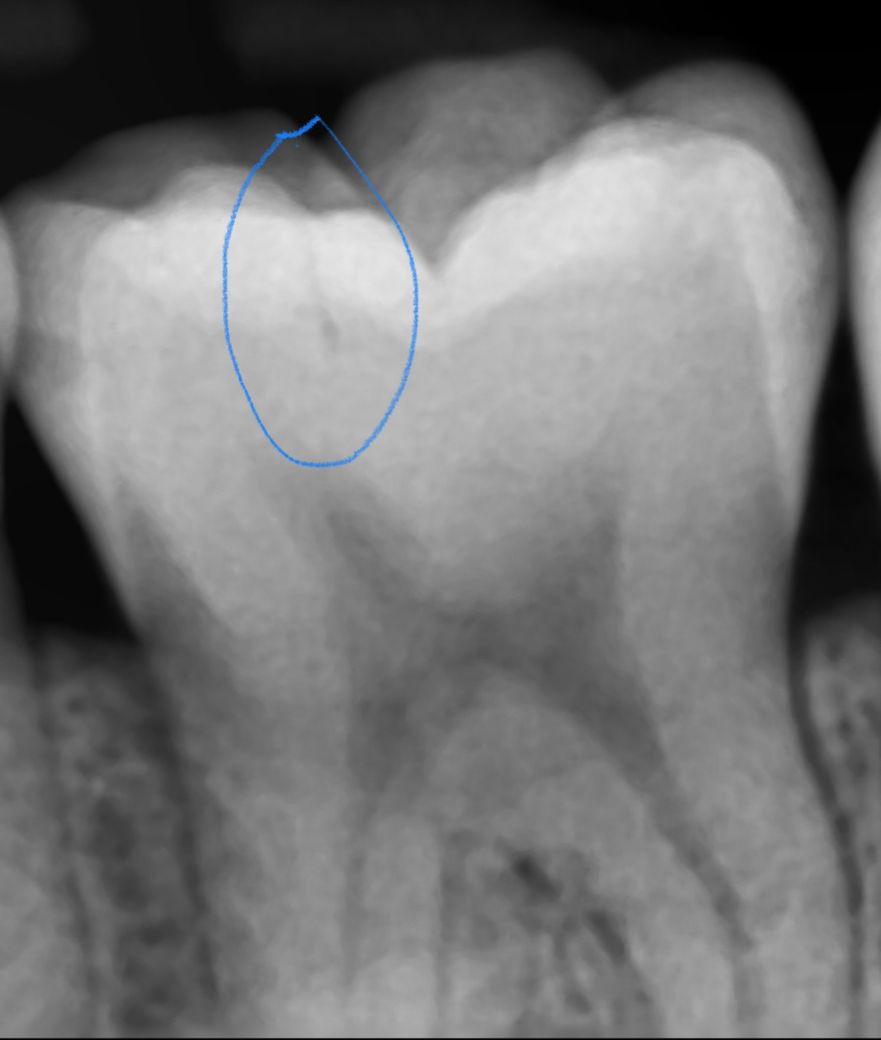

교합면에 이렇게 찍 줄나있는데 이건 뭔가요?

법랑질 넘어 상아질까지 찍 줄이 그어져있는데요 그저 교익방사선찍을때 찍힌 잔상인가요? 파노라마에서는 안보였는데 교익사진에서는 보여서 질문드려요 감사합니다

치아에 금이가서 저렇게 보일수도 잇고 예전에 치료한게 오래되서 틈이 생겨서 그렇게 보일수도 있습니다.

1. 파노라마 사진은 교익, 치근단 방사선 사진에 비해 해상도가 낮습니다.

2. 사진만으로는 크랙이 아닐까 의심되지만 확정적이진 않습니다. 금이 간 치아는 환자의 임상 증상, 메틸렌 블루 염색, 광투사, Q-ray 등으로 좀 더 정밀한 진단이 필요합니다.